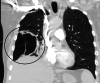

The Streptococcus anginosus group (SAG) consists of three bacteria (Streptococcus intermedius, Streptococcus constellatus, and Streptococcus anginosus) that are known commensals of the upper respiratory, digestive, and reproductive tracts. While a rare occurrence, these bacteria have the capability of causing devastating pyogenic infections and ensuing abscess formations. It is often difficult to distinguish this group as a contaminant or the offending organism (as it is often cultured in respiratory specimens); therefore, it is important to understand the risk factors, clinical presentation, and diagnostic findings that can provide a more accurate picture to identify the organism. Published literature pertaining to the SAG group has rarely documented any invasive surgical intervention that was undertaken for treatment. We describe a case of a 59-year-old male who presented for persistent chest pain and profuse productive cough weeks after he was diagnosed with a left lower extremity deep vein thrombosis and right-sided pulmonary embolism. The patient was found to have a rapidly evolving Streptococcus constellatus right middle lobe lung abscess complicated by a right hemithorax empyema. Management included an exploration of the right chest, decortication, parietal pleurectomy, and partial excision of the right middle lobe. Subsequently, the patient completed four weeks of antibiotics with ertapenem.